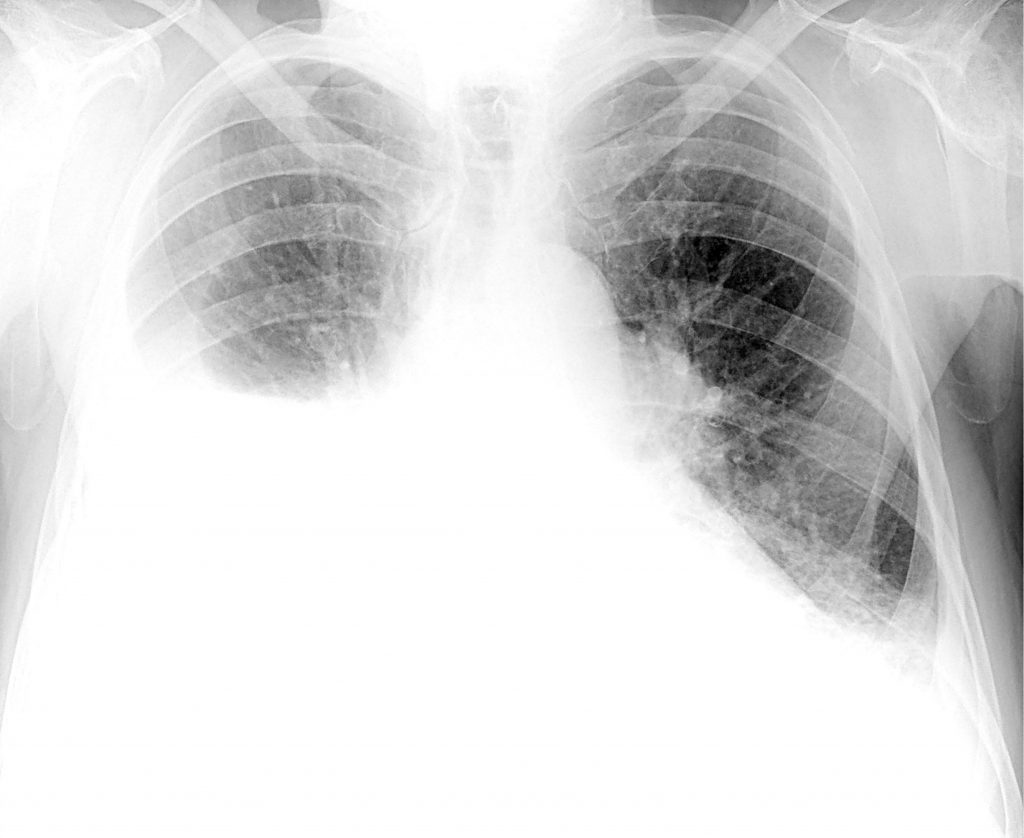

Возникающая в результате нарушения газообмена гипоксия, т.

е. кислородное голодание, отрицательно сказывается на работе всего организма,

поскольку все органы страдают от нехватки кислорода. На КТ или рентгеновских

снимках в таких ситуациях становятся заметными белые пятна, что еще называют

эффектом матового стекла. Впоследствии при развитии фиброза на снимках могут

визуализироваться особые затемнения, указывающие на пневмофиброз. Хотя подобные

изменения характерны не только для коронавирусной инфекции, но и для других

тяжелых бактериальных и вирусных пневмоний.